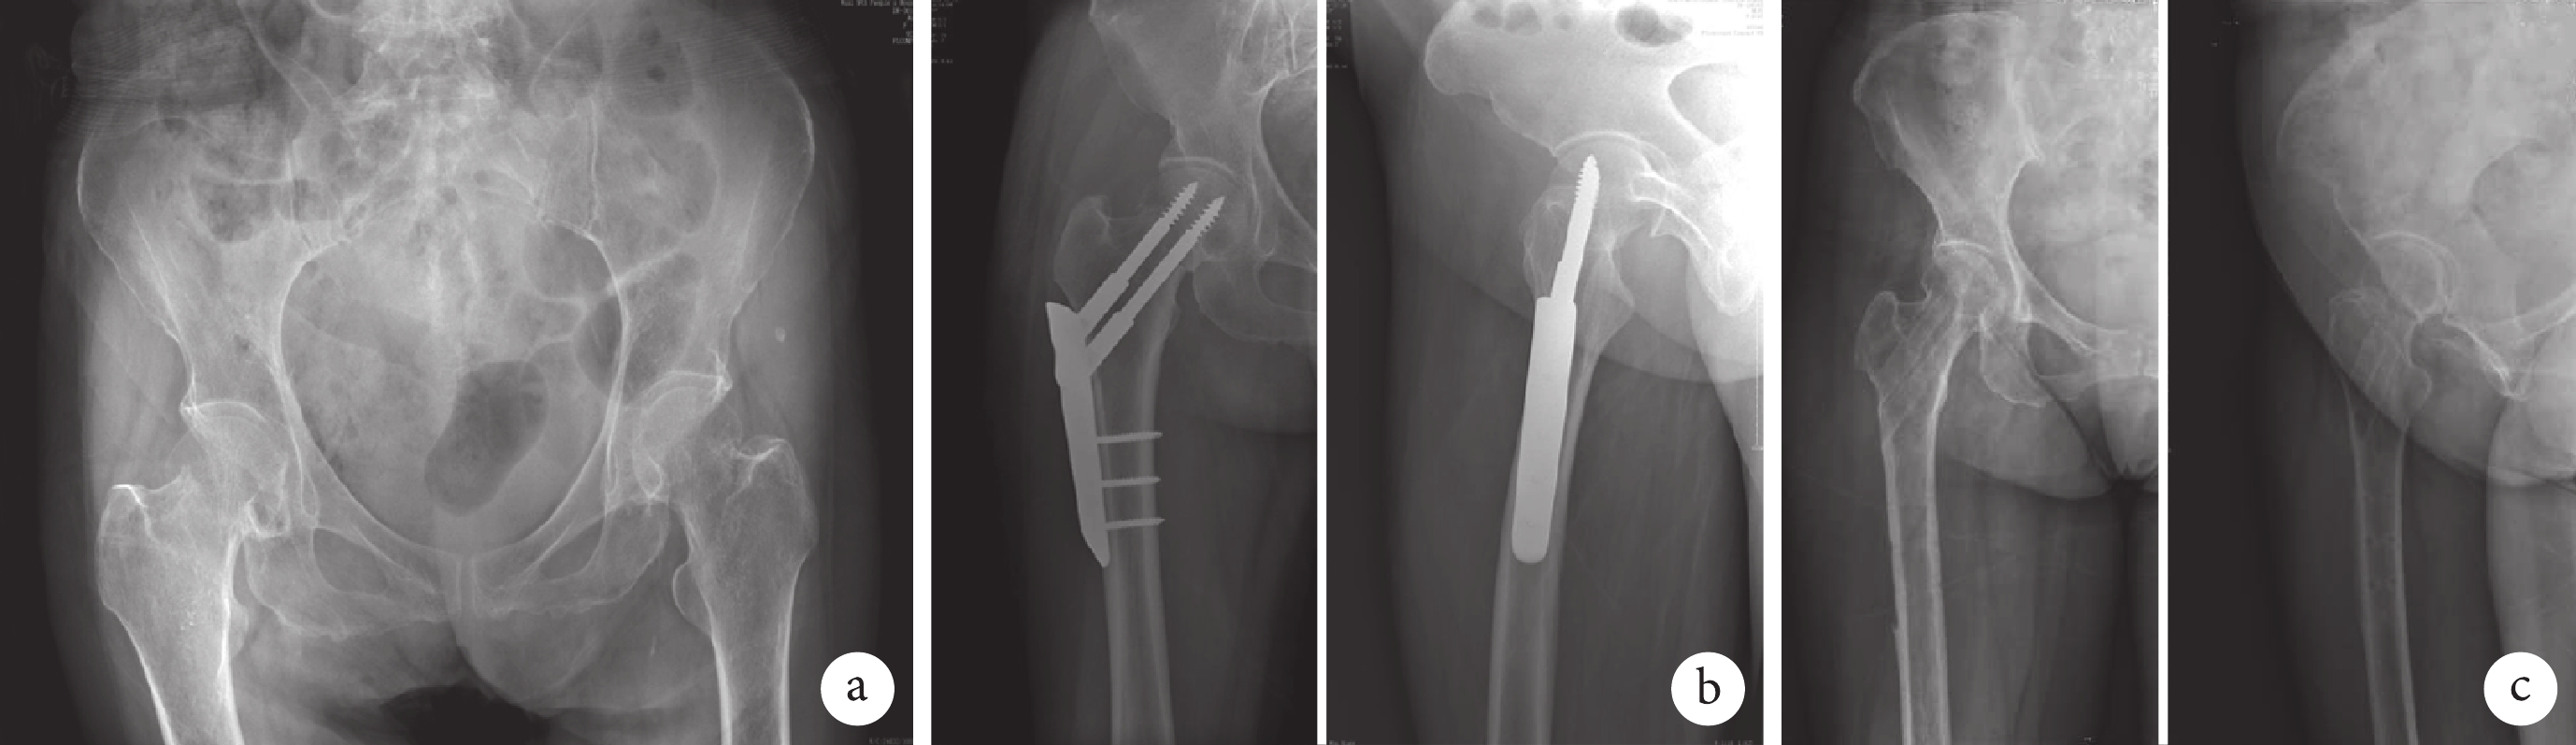

32 例患者均獲隨訪,隨訪時間 2.1~4.0 年,平均 2.7 年。除 2 例發生延遲愈合(均為移位的經頸型和頭下型骨折)外,無骨折不愈合和內固定失敗發生,骨折愈合時間 4~8 個月,平均 4.9 個月。見圖 1。12 例(37.5%)發生股骨頸短縮;3 例(9.4%)發生股骨頭壞死,均為移位的經頸型和頭下型骨折,其中 2 例行人工全髖關節置換、1 例行保守治療。術前、術后 3 個月、術后 2 年及末次隨訪時,髖關節 Harris 評分分別為(54.4±6.3)、(87.4±6.7)、(89.6±7.1)和(90.9±7.2)分,術后各時間點均較術前顯著改善,差異有統計學意義(P<0.05);術后各時間點間差異均無統計學意義(P>0.05)。末次隨訪時,根據 Harris 評分評價髖關節功能,獲優 15 例、良 12 例、可 5 例,優良率 84.4%。30 例患者(93.8%)能獨立行走,2 例(6.2%)不能獨立行走者中 1 例為股骨頭壞死保守治療者,1 例為合并膝骨關節炎和腰椎間盤突出癥者。本組不同年齡、Garden 分型、Singh 指數和 Garden 對線指數患者間術后髖關節功能的構成差異均無統計學意義(P>0.05),見表 1。

a. 術前;b. 術后 1 年正側位示股骨頸短縮愈合;c. 術后 2 年取出內固定物后正側位示骨折愈合良好

Figure1. X-ray films of a 77-year old female patient with right femoral neck fractures caused by falling injury (Garden type Ⅳ and Singh index level Ⅳ)a. Preoperative view; b. Anteroposterior and lateral views showed shortening healing of femoral neck at 1 year after operation; c. Anteroposterior and lateral views showed fractures healed well after removal of internal fixation at 2 years after operation